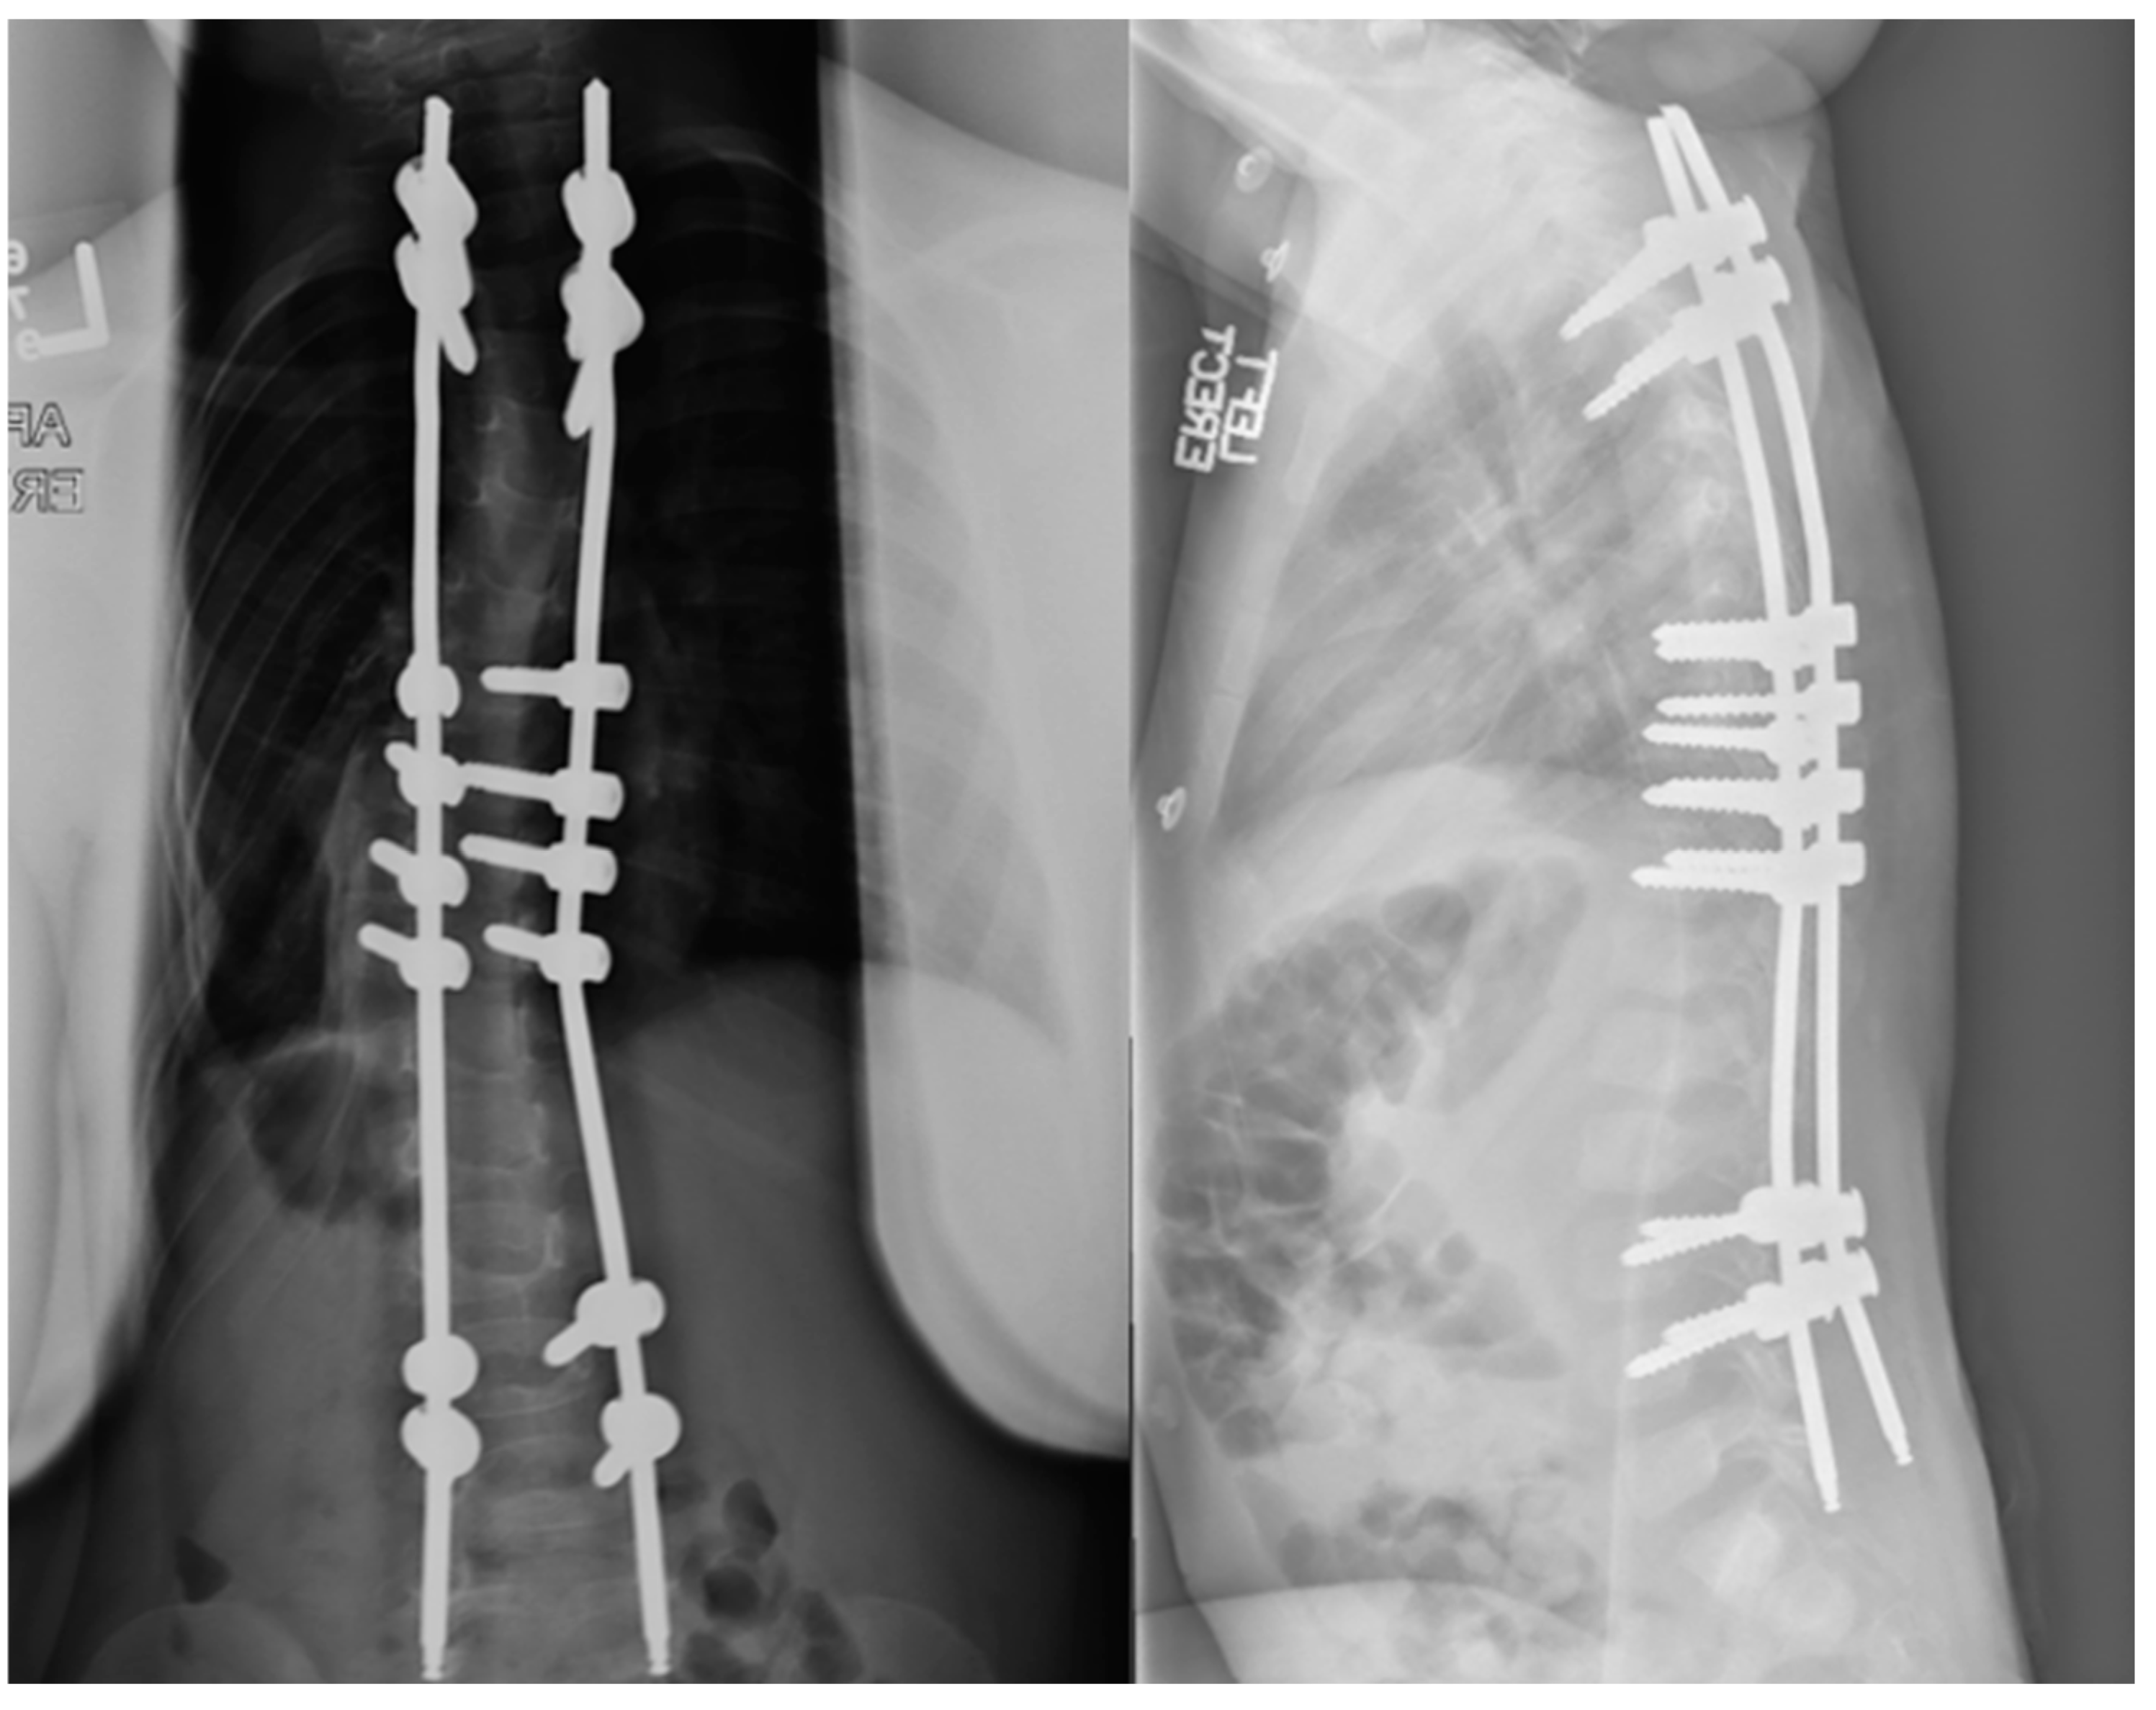

Initially developed for idiopathic scoliosis curves from 45–60 degrees, vertebral body tethering has recently been explored for older early onset patients [61,62,63]. In this population of 8–11 with Sanders scores less than four, dubbed “Tweeners”, VBT was shown to be as effective as MCGRs and PSF for correction of deformity. A clinical example is shown in Figure 6. In a study supplying direct comparison amongst the three, major scoliosis curve correction was seen in all three groups including by 41.1% with VBT, 52.2% with PSF, and by 27.4% with MCGRs. This same study demonstrated high rates of unplanned operations in MCGRs compared to PSF and VBT with 21.6% of MCGR, 16.2% of VBT, and 7.1% of PSF patients undergoing at least one unplanned revision. Technical considerations exist for VBT including instrumentation sizes that may not be appropriate for the smallest patients. Applying VBT to younger patients may not fully prevent the need for definitive fusion, however, it could prevent the progression of lumbar curves and make selective thoracic fusions more successful and limit lumbar instrumentation, although this is largely theoretical and should not diminish the morbidity of a secondary surgery. VBT does confer technique-specific complications including those associated with thorascopic and anterior surgery, overcorrection, and the risk of cord breakage which is seen in up to 50% of thoracic tethers and is as high as 70–80% in the lumbar spine [64]. While there are few studies examining the application of tethering in the early onset population, available data suggest it is an option in older early onset patients.

Figure 6. Pre- and postoperative imaging of a female patient with early onset scoliosis treated with anterior vertebral body tethering.